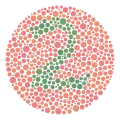

Een ishiharatest. Niet-kleurenblinden ontwaren op deze plaat duidelijk het getal 74. | ||||

Kleurenblindheid is meestal een erfelijke aandoening, en de meest voorkomende vorm van kleurenblindheid is geslachtsgebonden. Er bestaan ook verworven vormen, meestal als gevolg van vergiftigingen, zoals door gebruik van bepaalde geneesmiddelen. Om kleurenblindheid op te sporen worden kleurenvisietesten uitgevoerd, zoals de Ishiharatest. Er bestaat geen behandeling voor kleurenblindheid, maar er zijn wel enkele hulpmiddelen die ondersteuning bieden, zoals speciaal corrigerende brilglazen. Milde vormen van kleurenblindheid hebben vaak geen significante invloed op het dagelijks leven en kleurenblinden ontwikkelen meestal vanzelf aanpassingen om de afwijking te compenseren.

- De ishiharatest

- Hiermee wordt de kleurenblindheid nagegaan aan de hand van een schijf met gekleurde bolletjes. De patiënt moet zeggen welke cijfers er in het bolletjespatroon verborgen zitten. Hiermee worden alleen rood/groen-stoornissen (protan/deutan) getest.